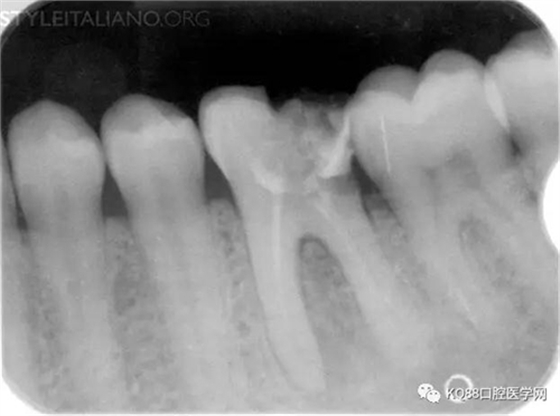

Img. 3 - The frequency of post-endodontic pain is higher in teeth with periapical or periradicular lesions. Infected debris can be forced in the periradicular tissue through a resorpted apex, thus generating acute inflammation. Creating a glide path prior to instrumentation and using a step-down technique can reduce the amount of extruded debris.